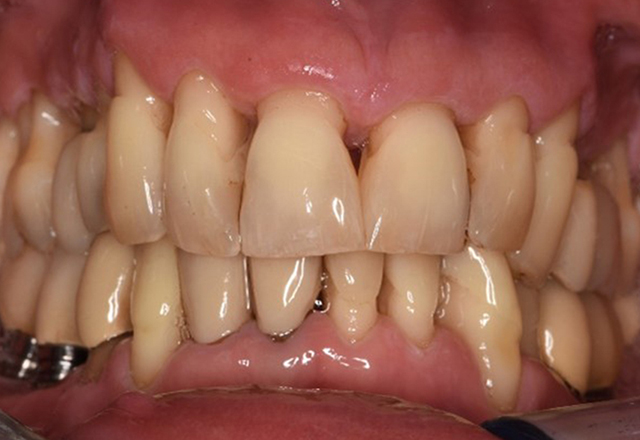

In the medical history, the 55-year-old patient states that he has no systemic disease and is not taking any medication. The patient’s lifestyle is similarly unremarkable. The patient has a few tooth restorations and two implants (2nd and 4th quadrants). On the basis of current findings, gingivitis is identified in an otherwise stable periodontal condition on the reduced periodontium (stage III, grade A). more

The healthy patient with pre-existing periodontal disease & peri-implantitis

A 52-year-old patient presents at a preventive care session. The patient has no systemic disease and is not taking any medication. He has had various dental treatments and also has two active carious lesions. In addition, the patient has four implants (2nd, 3rd and 4th quadrants). He is revealed to have early periodontal disease (stage IV, grade B). His periodontal condition is stable; a probing depth of Probing depths (ST) of 5 mm is only evident at the implant in region 36. Gingivitis is also identified. more

The healthy patient with early periodontal disease

The 68-year-old patient has no general health conditions and is not taking any medication that may be relevant to her oral health, and her lifestyle does not pose any particular risk. The patient has two dental implants (3rd quadrant, for five years) and a previous case of periodontal disease (stage IV, grade B periodontitis) with tooth loss. Currently the periodontal conditions are stable. However, periodontitis significantly increases the biological complications of implantations and there is a risk of implant loss (21). Four recommendations can be determined for the prophylaxis session. more